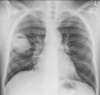

NÓDULO SOLITÁRIO

MELHOR MODO DE VERIFICIAR MALIGINIDADE É VER O CRESCIMENTO NOS ULTIMOS DOIS ANOS

PRESENÇA DE LESÃO PERIFÉRICA, AQUAL , É REALIZADA BX COM VIDEOTORACOSCOPIA.